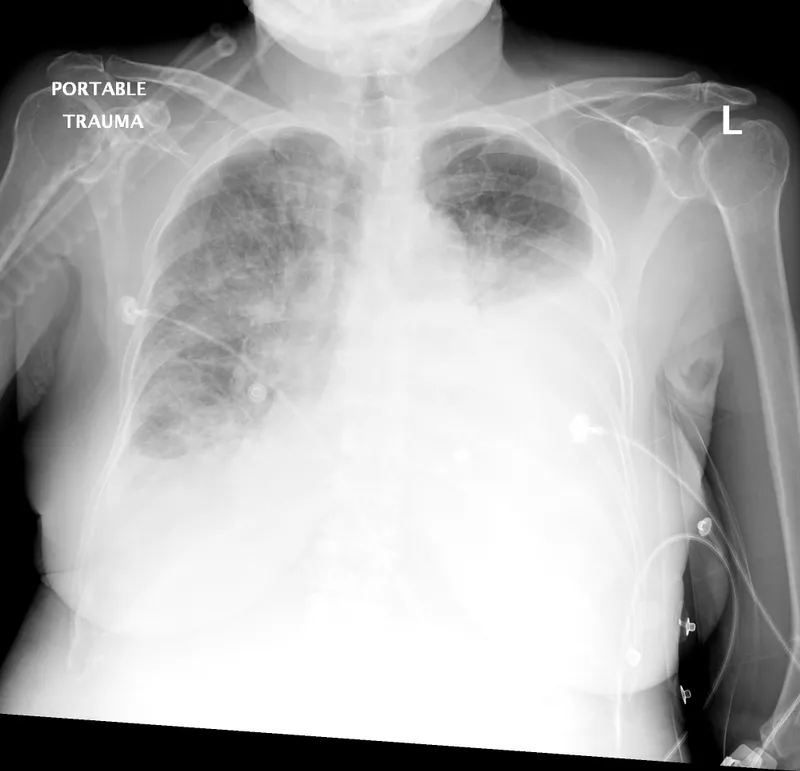

| CXR | Normal/Hampton's/Westermark | Pleural line | Bilat. infiltrates/Kerley B | Hyperinflation/Normal |

- Initial Investigations: Pulse oximetry, CXR, ECG, ABG ($P(A-a)O_2$).

- Further: CBC, D-dimer, BNP/NT-proBNP, Troponins, Spirometry/PFTs, Echo, CT chest (CTPA, HRCT).